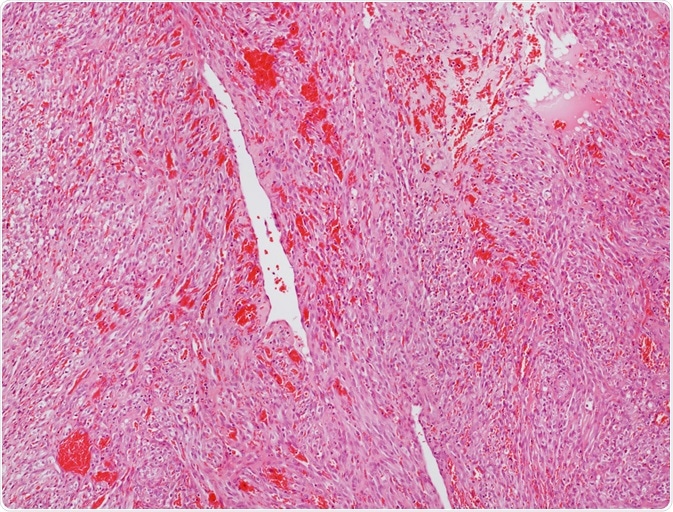

Image Credit: Convit / Shutterstock.com